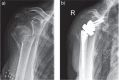

Since the introduction of reverse total shoulder arthroplasty (RTSA) in 1987 (in Europe) and 2004 (in the United States), the number of RTSAs performed annually has increased.Although the main indication for RTSA has been rotator cuff tears, indications have expanded to include several shoulder conditions, many of which involve dysfunction of the rotator cuff.RTSA complications have been reported to affect 19% to 68% of patients and include acromial fracture, haematoma, infection, instability, mechanical baseplate failure, neurological injury, periprosthetic fracture and scapular notching.Current controversies in RTSA include optimal baseplate positioning, humeral neck-shaft angle (135° versus 155°), glenosphere placement (medial, lateral or bony increased offset RTSA) and subscapularis repair.Improvements in prosthesis design, surgeon experience and clinical results will need to occur to optimize this treatment for many shoulder conditions. Cite this article: EFORT Open Rev 2018;3:58-69 DOI: 10.1302/2058-5241.3.170044.